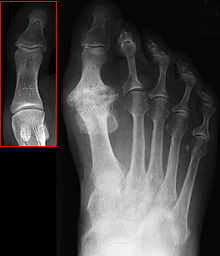

Foot.png

Hallux not labeled but visible at upper left.